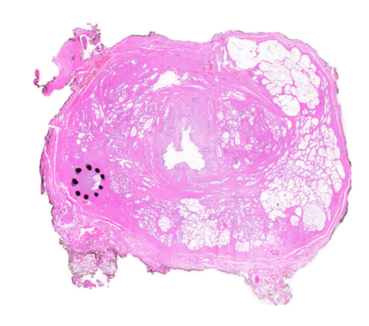

Whole-mount section of an

insignificant prostate cancer (haematoxylin and eosin staining plus immunostaining).